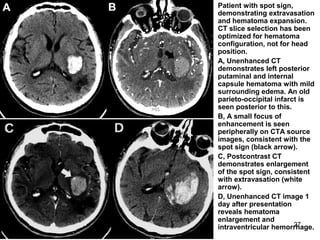

• Patient with spot sign,

demonstrating extravasation

and hematoma expansion.

CT slice selection has been

optimized for hematoma

configuration, not for head

position.

• A, Unenhanced CT

demonstrates left posterior

putaminal and internal

capsule hematoma with mild

surrounding edema. An old

parieto-occipital infarct is

seen posterior to this.

• B, A small focus of

enhancement is seen

peripherally on CTA source

images, consistent with the

spot sign (black arrow).

• C, Postcontrast CT

demonstrates enlargement

of the spot sign, consistent

with extravasation (white

arrow).

• D, Unenhanced CT image 1

day after presentation

reveals hematoma

enlargement and

intraventricular hemorrhage.